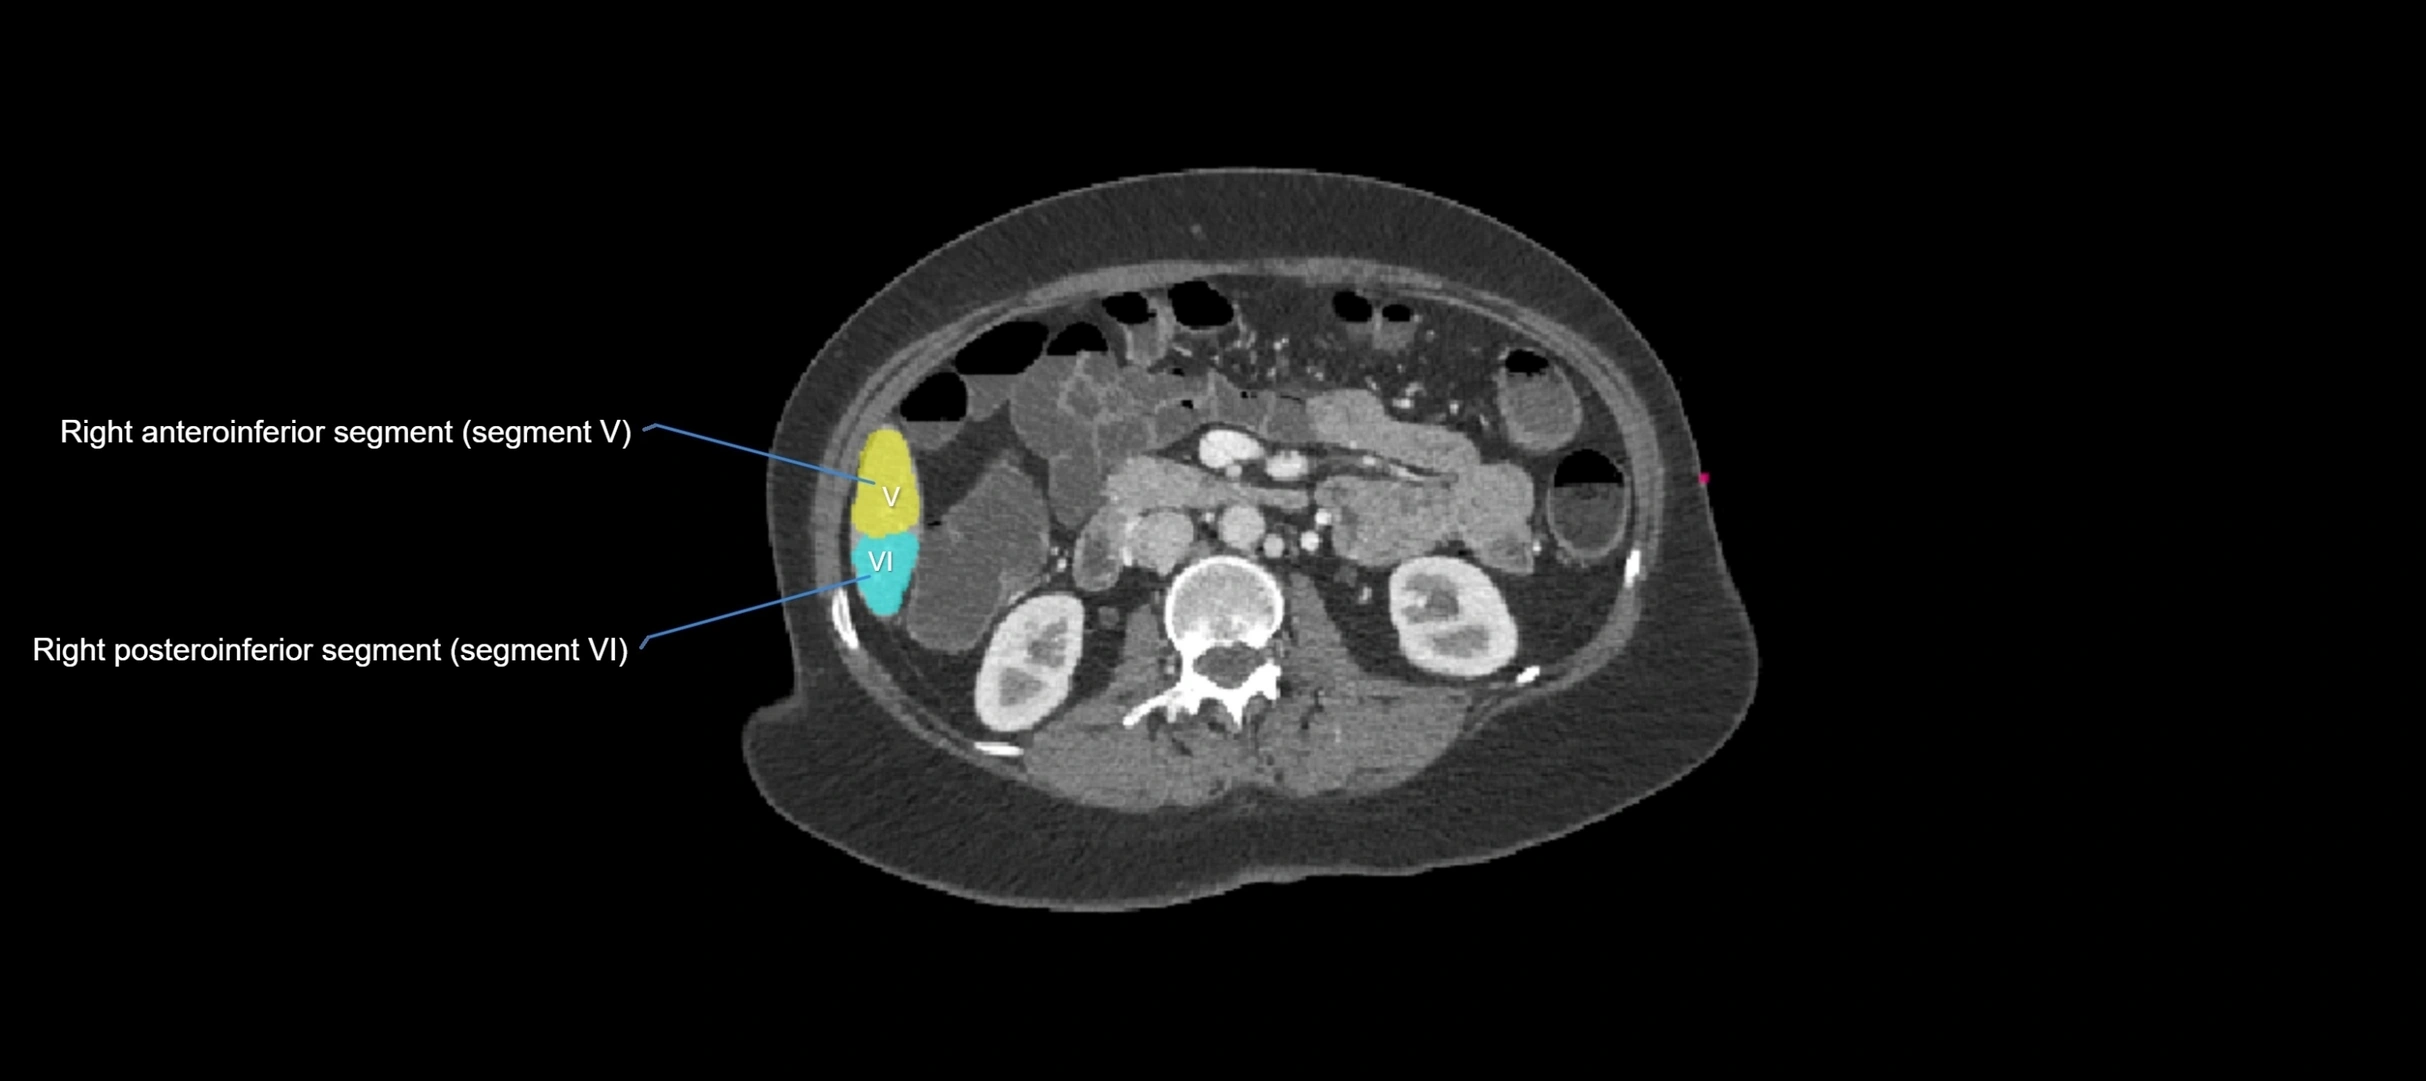

The caudate lobe of the liver is a distinct anatomical subdivision of the liver, designated as segment I in Couinaud’s classification. It lies on the posterior surface of the liver, between the fissure for the ligamentum venosum (left boundary) and the groove for the inferior vena cava (IVC) (right boundary). Superiorly, it is related to the posterior liver surface, and inferiorly it is separated from the left lobe by the porta hepatis.

CT Image

image